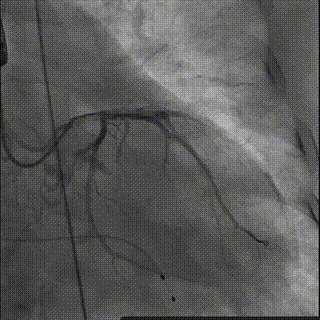

图片

球囊后扩

术后造影